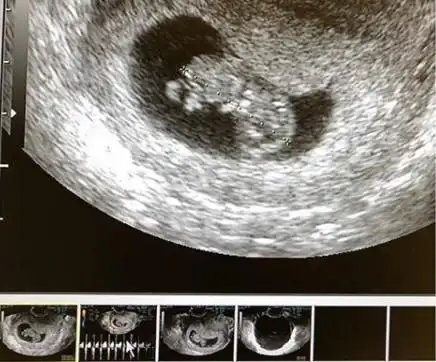

槿汐孙茜晒b超照宣布怀孕感谢生命的力量

15周大的胎儿b超影像

韩女星朴嘉熙三年抱俩晒出b超照宣布怀二胎